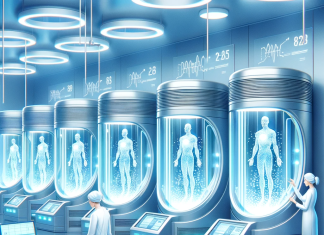

Prin medicină înțelegem ”arta de a vindeca”, adică un univers foarte larg de cunoștințe, dedicate studierii corpului omenesc și conservării sănătății acestuia. În principiu, sunt mai multe ramuri: etiologia (studierea cauzelor dereglărilor din corp sau a bolilor), patologia (analizarea manifestărilor clinice și a efectelor asupra corpului), diagnosticul (identificarea problemelor), terapia (tratarea problemelor în vederea însănătoșirii corpului) sau profilaxia (acțiunile de prevenire a îmbolnăvirilor).

Știința medicinei se bazează pe multe științe conexe, începând cu anatomia, biologia, fizica sau chimia, până la fiziologie, farmacologie sau radiologie. În funcție de istorie și civilizații, avem două mari categorii ale medicinei: cea modernă (faptică) – fondată pe fapte și dovezi experimentale, specifică lumii occidentale și Europei răsăritene; respectiv medicina alternativă (cum este cea naturistă, de exemplu), practicată în special în zonele nedezvoltate sau în curs de dezvoltare, dar care, în multe situații, produce rezultate bune, ca și cea convențională (bazată pe produse farmaceutice, pe utilizarea statisticii și pe teorii ale studiului clinic).

Există două mari categorii de specialități clinice: chirugicale și medicale (de la anestezie și terapie intensivă, boli infecțioase sau cardiologie până la endocrinologie, pediatrie, neurologie sau dermatovenerologie). Pe lângă acestea, mai există specialități paraclinice (de exemplu medicina legală sau epidemiologia), dar și domeniul dentar. Cu alte cuvinte, medicina este un teritoriu extrem de vast, în care noile descoperiri sunt foarte numeroase.